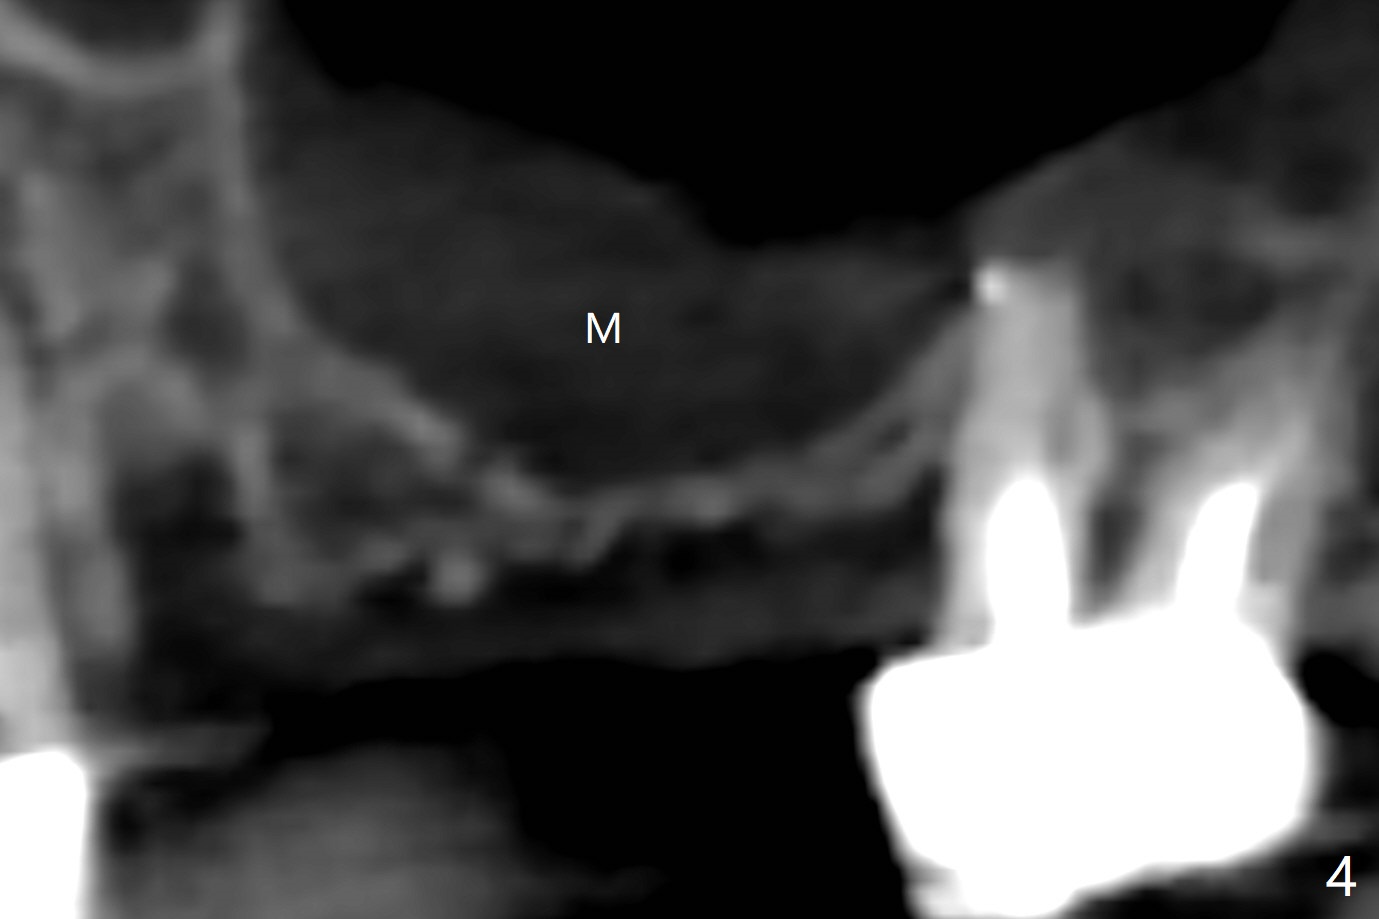

A 68-year-old timid woman is considering implant at #14 twenty months post cementation of #13 and 14 crown (Fig.1). Because of the narrow buccopalatal width (Fig.2 CT coronal section, B: buccal), a 4 mm implant (blue line) seems to be appropriate for the site (Fig.1). After crestal incision and flap reflection, a diamond round bur is used to thin the sinus floor until the bluish membrane is barely visible. An osteotome (Magic Sinus Lifter) is used for penetration. Water lift will be conducted if necessary, considering the already thickened sinus membrane (Fig.3 (CT sagittal section) M). Insert the first PRF membrane, followed by bone graft (not too sticky) repeatedly. Use sensor 1 to confirm lift degree. Try a 4x7 mm dummy FC to test stability. Place a definitive one (probably Magicore) if indicated. Use a second PRF membrane before closure of the wound. After nearly 15 month consideration (including coronovirus), the patient decides to get it done. With incision (Fig.4) and Marking Drill (Fig.5, the sinus membrane barely visible in the middle of the osteotomy (dimple, Fig.6 (black triangle)), the sinus floor does not break upon Magic Sinus Lifter). Later the patient complains of discomfort with tapping. In fact Magic Drill (similar to trephine bur, Fig.7) is used to break into the sinus without membrane perforation (Fig.8). Remember the thick membrane (Fig.2,3). In fact the fractured fragment is attached to the membrane (Fig.9 red lines, green sticky fracture). A small curette is used to further separate the membrane from the bony wall (Fig.10) before insertion of a small piece of PRF and sticky bone. When a 4.5x7 mm dummy implant is incompletely placed with stability (<10 Ncm), the membrane is stretched over the bone graft (Fig.11 M). After removal of the dummy, the major remaining piece of PRF (from 9 cc vial) and more allograft are placed before inserting a definitive implant (same size) with 15 Ncm; still the used to be thick membrane remains intact and stretched (Fig.12 M). The implant is equicrestal buccal, while slightly supracrestal palatal. To prevent implant dislodgement into the sinus and bone graft, a final abutment is placed (Fig.12). The wound is closed with 4-0 PGA, perio glue and perio dressing. The latter dislodges 3 days postop. The wound seems to be healing. No dressing is reapplied.